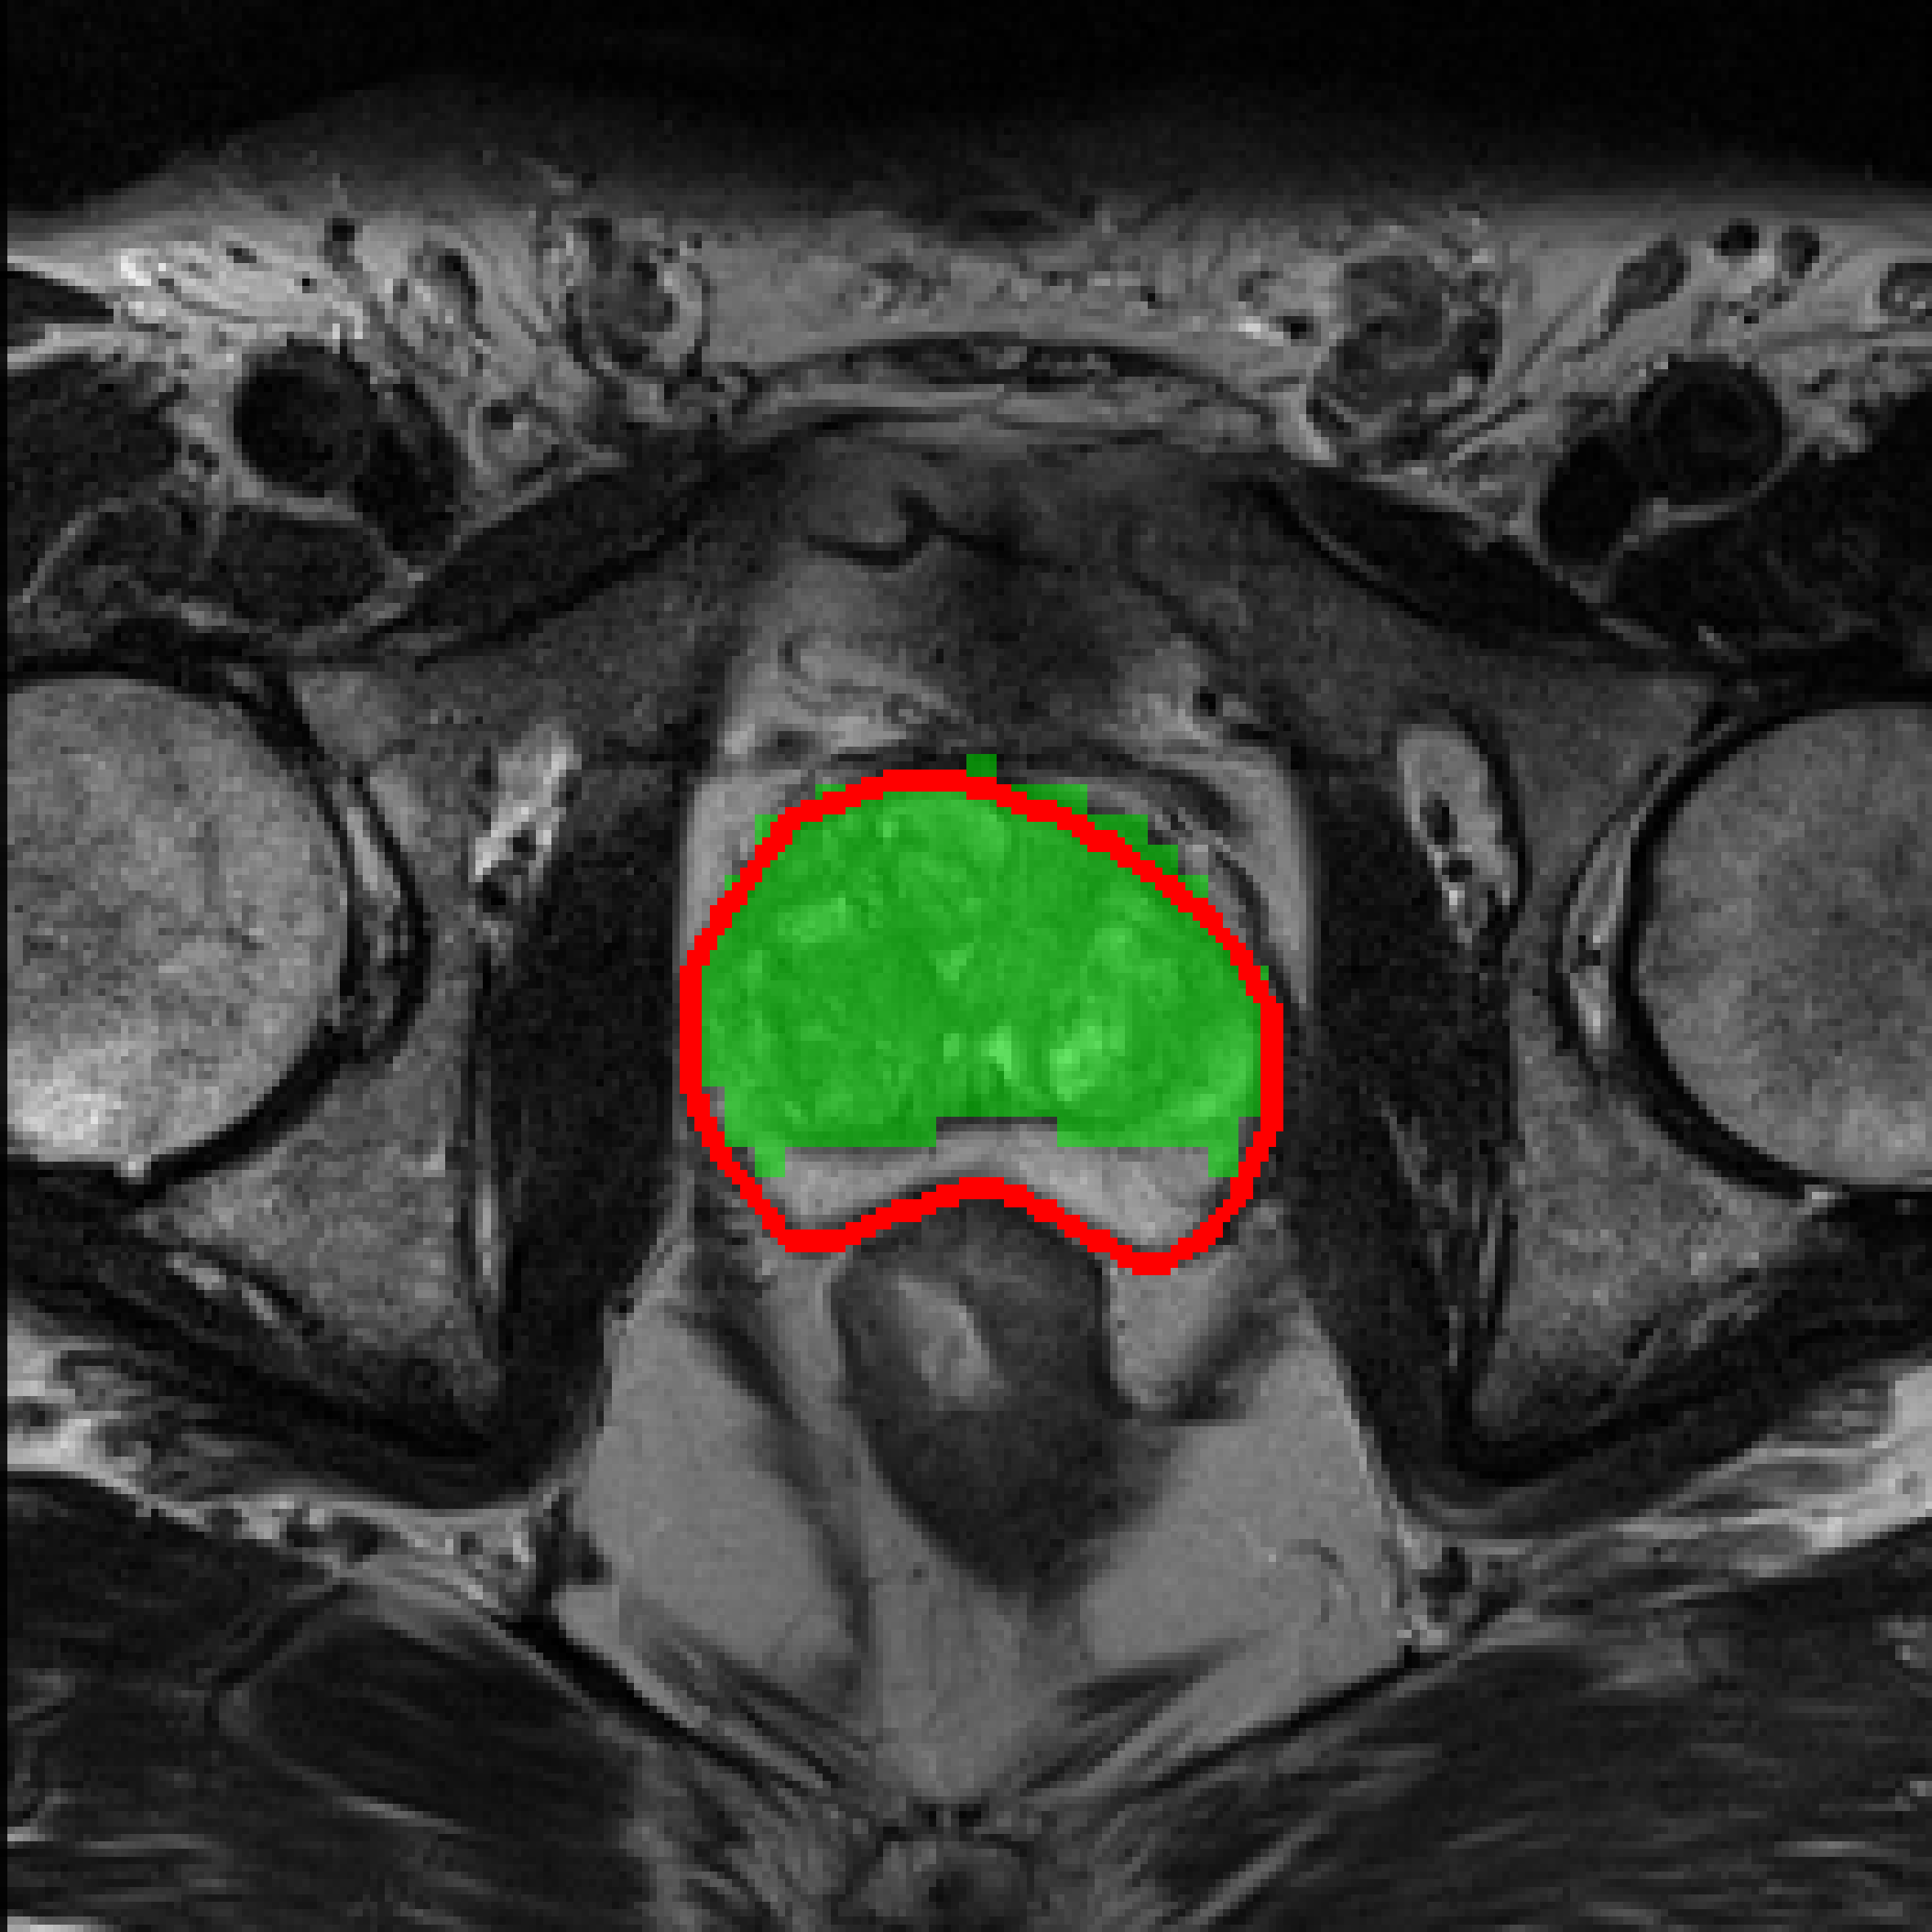

Table 3: Qualitative results of different methods, \Circle and \CIRCLE denote groundtruth and predicted mask, respectively.

SAM MedSAM SAM-Med2D CPC-SAM KnowSAM Ours

5% Promise [Uncaptioned image] [Uncaptioned image] [Uncaptioned image] [Uncaptioned image] [Uncaptioned image] [Uncaptioned image]

10% Promise [Uncaptioned image] [Uncaptioned image] [Uncaptioned image] [Uncaptioned image] [Uncaptioned image] [Uncaptioned image]

5% Colon [Uncaptioned image] [Uncaptioned image] [Uncaptioned image] [Uncaptioned image] [Uncaptioned image] [Uncaptioned image]

10% Colon [Uncaptioned image] [Uncaptioned image] [Uncaptioned image] [Uncaptioned image] [Uncaptioned image] [Uncaptioned image]

For the qualitative results shown in Tab. 3, our method consistently produces more accurate and compact segmentation results for most cases in the PROMISE12 and COLON datasets, effectively capturing the prostate and polyp boundaries while suppressing background noise. In contrast, other approaches tend to over-segment the target regions, leading to the inclusion of irrelevant surrounding tissues. These results visually demonstrate the robustness of our method in handling diverse anatomical variations.